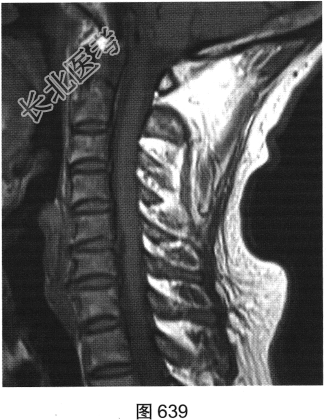

- 多项选择题3.[提示]患者保守治疗2个月后复查MRI,见图638~图642。复查的MRI图像与前次比较, 有哪些影像学变化( )

A、病变明显变小

B、颈前软组织强化

C、增强后未见强化

D、增强后可见小片状强化

E、C

间盘信号有变化F、硬膜囊及颈髓受压缓解

关注下方微信公众号,搜题查看答案

- 多项选择题4.根据复查的MRI表现,该患者可能的诊断是( )

A、椎间盘脱出、髓核游离

B、硬膜外血肿

C、神经纤维瘤

D、后纵韧带骨化

E、神经鞘瘤

F、脊柱淋巴瘤